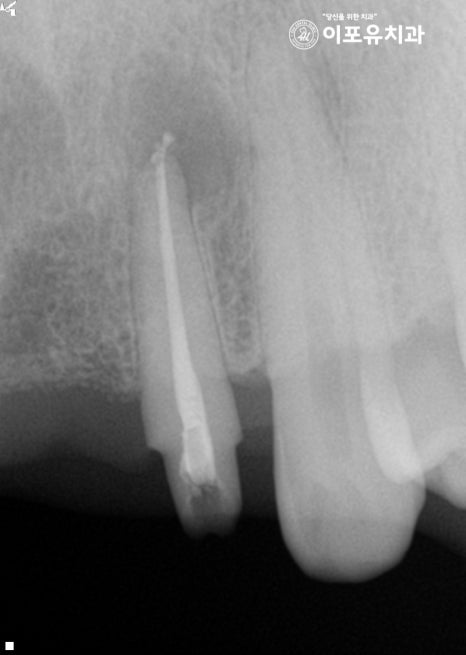

상악 전치부 주변에 고름이 잡혔기 때문에

이곳의 원인을 정확하게 찾은 뒤

신경치료 를 진행하는 것이 중요한데요.

고름이 퍼져 있는 길을 찾아보니

양쪽 두 번째 앞니에 퍼져 있는

염증을 확인할 수 있었습니다.

따라서 # 12 # 22 근관 세척 및 충전 과정을 진행하여

현재 나타난 제일 큰 문제를 개선하는 것이 좋습니다.

근관 내부를 깨끗하게 청소한 뒤

소독과정까지 확실하게 마쳐야 됩니다.

이후 충전재를 사용하여 뿌리 끝까지 밀폐하여

2차 감염의 확률을 줄여줍니다.